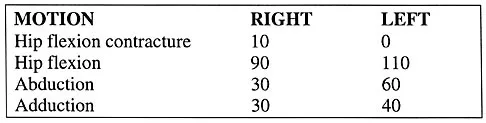

Question 30

The parents of a previously healthy 3-year-old child report that she refused to walk on awakening. Examination later in the day reveals that the patient can walk but with a noticeable limp. She has a temperature of 99.5 degrees F (37.5 degrees C). Range of motion measurements are shown in Figure 50. An AP pelvis radiograph is normal. Laboratory studies show a WBC count of 9,000/mm3 and an erythrocyte sedimentation rate of 10 mm/h. Management should consist of

Explanation